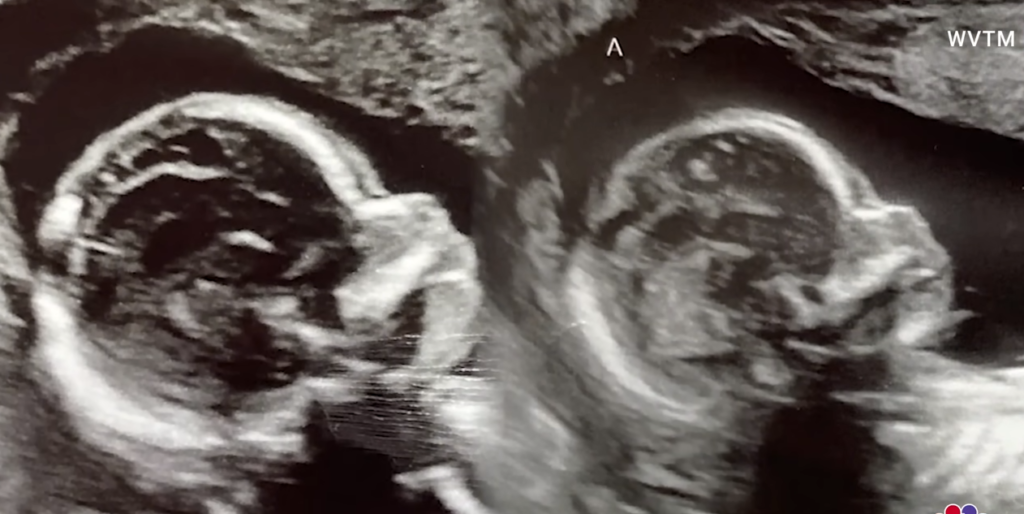

Την Τρίτη, 14 Νοεμβρίου, μοιράστηκε εικόνες από εξετάσεις που έκανε και «μερικούς υπερήχους από χθες» των δύο μωρών στη μήτρα της. «Τα κορίτσια πέρασαν τον υπέρηχο BPP αυτή την εβδομάδα! Όλα φαίνονταν υπέροχα», αναφέρει.

Η διπλή εγκυμοσύνη αποκαλύφθηκε κατά τη διάρκεια μιας συνηθισμένης επίσκεψης για τον υπέρηχο των οκτώ εβδομάδων τον Μάιο, κατά τον οποίο η Kelsey, η οποία είναι ήδη μητέρα τριών παιδιών, έμαθε πως κυοφορεί δίδυμα, αλλά ότι υπήρχε ένα έμβρυο σε κάθε μήτρα της.

Οι εγκυμοσύνες με δύο μήτρες είναι εξαιρετικά σπάνιες και επιφυλάσσουν πολλούς κινδύνους και επιπλοκές, αλλά η Kelsey -ευτυχώς- δεν αντιμετωπίζει κάποια επιπλοκή μέχρι στιγμής. Τώρα ελπίζει να προχωρήσει στον τοκετό και να γεννήσει το μωρό Α και το μωρό Β, ή «τα κορίτσια» όπως τα αποκαλεί με στοργή, με ημερομηνία γέννησης τα Χριστούγεννα.